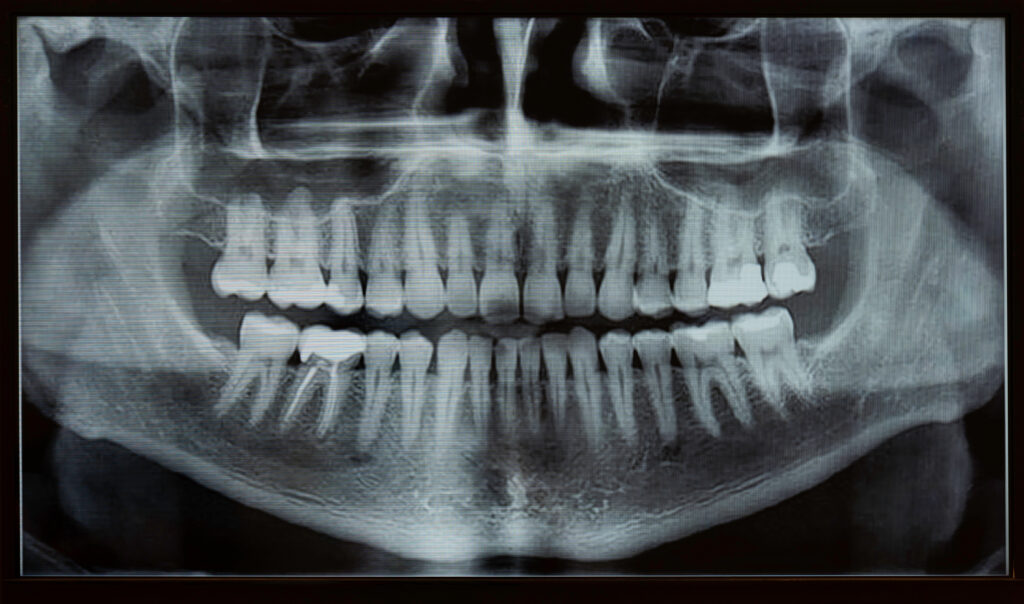

①レントゲン撮影

レントゲン写真を撮ることで、直接目では見ることのできない部分の状況を知ることができます。 歯周病は、歯ぐきの内側の見えない部分で進行して、骨が溶かされ減少する病気です。 そのためレントゲン写真を撮って、歯を支える骨の状態を把握することが必ず必要です。 歯周病が進行すると、歯を支える骨を溶かしてしまうのですが、レントゲン写真にはその骨の高さ等が写りますので、現在の骨の状況を正しく知ることが可能です。 また、歯ぐきの奥の歯石もレントゲン写真には写ります。 歯石が歯ぐきの奥についたままにしていると、歯周病の治療の妨げになります。 もし、レントゲン写真なしで検査をすると、隠れて進行している歯周病を見逃してしまうこともありますので、重要な検査となっています。